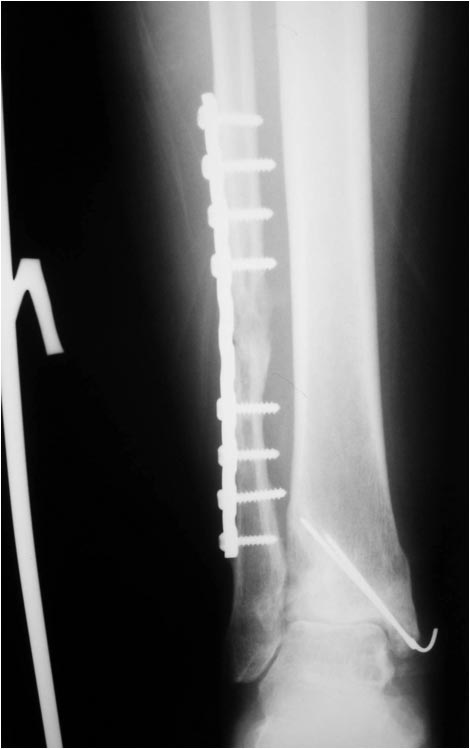

Мужчина, 1987 г.р. получил травму 10.2014. ДТП. Закрытый двухлодыжечный перелом костей костей левой голени, перелом заднего края большеберцовой кости с подвывихом стопы кзади, кнаружи.

Наложен дистрактор. Операция 10.2014: закрытая репозиция, остеосинтез спицами, винтами. В дальнейшем произошло ожидаемое усугубление нарушений взаимоотношений в голеностопном суставе.

Мне кажется, что вопрос, поставленный Вами: "Возможно ли одномоментно устранить подвывих или только на аппарате Иллизарова?", отражает не совсем ясное понимание ситуации. Что значит устранить подвывих? А пластику ложных суставов внутренней лодыжки и заднего края большеберцовой кости не нужно делать? И ось голеностопного сустава нужно исправлять. То есть делать остеотомию наружной лодыжки (если она срослась, по снимку не очень понял). Артродез голеностопного сустава в такой ситуации очень сложен. Если же добиться сращения всех переломов в правильном положении, артродез вполне можно отсрочить на несколько лет, что для молодого пациента достаточно важно. Но в конечном счете все определяется Вашим умением и ясным представлением того, чего Вы хотите добиться своей операцией. Во вложении - в чем-то похожий случай. Оперировал эту пациентку 23 лет 11 лет назад через 8 месяцев после похожего на представленный Вами остеосинтез. На первой операции перелом малоберцовой кости в нижней трети был просто не замечен. За счет восстановления оси быстро развившийся артроз протекал благоприятно. В результате артродез был выполнен только в прошлом году, через 10 лет после второй операции. И боли беспокоили пациентку только в течение года перед артродезом.